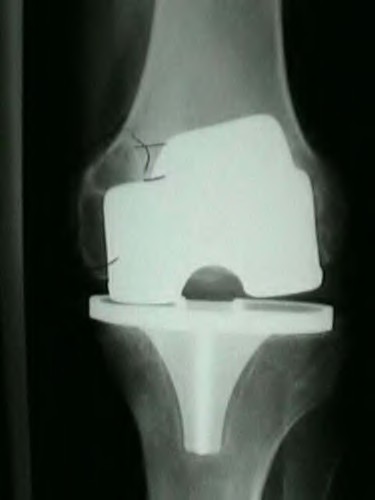

A 65-year-old woman with painful knee arthritis and the deformity seen in Figure A, is scheduled to undergo a total knee arthroplasty. All the following are risk factors for a post-operative peroneal palsy EXCEPT:

The clinical presentation is consistent with end-stage arthritis in a valgus knee. All of the factors listed are risk factors for peroneal nerve palsy EXCEPT female gender, which is not a risk factor.

Peroneal nerve palsy is a potential serious complication of TKA in patients with a pre-operative valgus knee deformity. Peroneal nerve palsy is likely caused by lengthening of the lateral aspect of the knee and subsequent traction on the peroneal nerve. It is generally recommended that patients be evaluated

carefully for symptoms postoperatively. If peroneal nerve palsy symptoms are discovered, the knee should be flexed to relax the tension that is effectively being placed on the nerve. If peri-operative nerve exploration or decompression is undertaken, the posterior border of the biceps-femoris tendon is the proper site of identification.

Idusuyi et al. published a retrospective review of 32 postoperative peroneal nerve palsies in thirty patients in which they identified possible risk factors. Prior proximal tibial osteotomy, lumbar laminectomy (thought to be a “double-crush” phenomenon), and preoperative valgus alignment of 12 degrees or more were all identified as risk factors. Other concerns included epidural anesthesia for postop pain control, preoperative flexion contractures and tourniquette time greater than 120 minutes also increased concern.

Favorito et al reviewed valgus total knee arthroplasty and reported that the most common complications of patients with a valgus deformity include: tibiofemoral instability (2% to 70%), recurrent valgus deformity (4% to 38%), postoperative motion deficits requiring manipulation (1% to 20%), wound problems (4% to 13%), patellar stress fracture or osteonecrosis (1% to 12%), patellar tracking problems (2% to 10%), and peroneal nerve palsy (3% to 4%).

Figure A demonstrates and AP radiograph of the knee showing end-stage arthritis with severe lateral compartment narrowing.